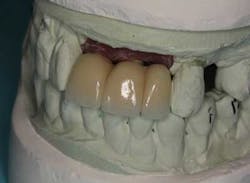

From a restorative perspective, now that the implants were placed in a restoratively driven manner, the main considerations were to address the patient’s malocclusion and correct her edge-to-edge bite while delivering optimal esthetics. In order to accomplish this goal, a framework was fabricated with a wax-up on the casts. (Fig. 14) By utilizing this method at the framework try-in visit, we were able to give the patient an extremely accurate preview of what her final prosthetic would look like.